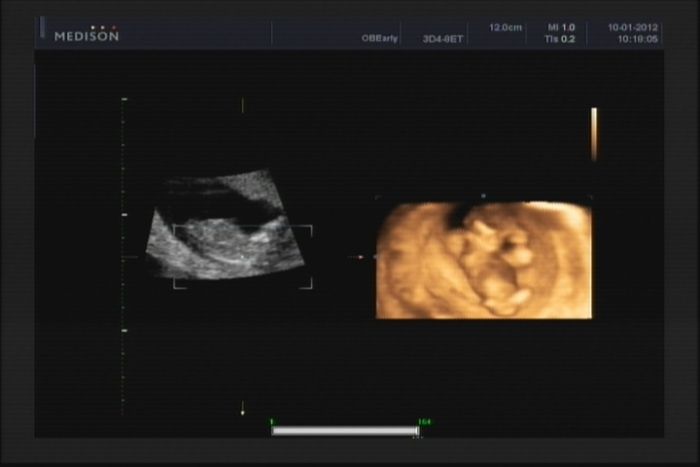

Moc pěkné fotečky,hlavně ta 3D.My půjdeme potom ve 25-28tt.na 3D video